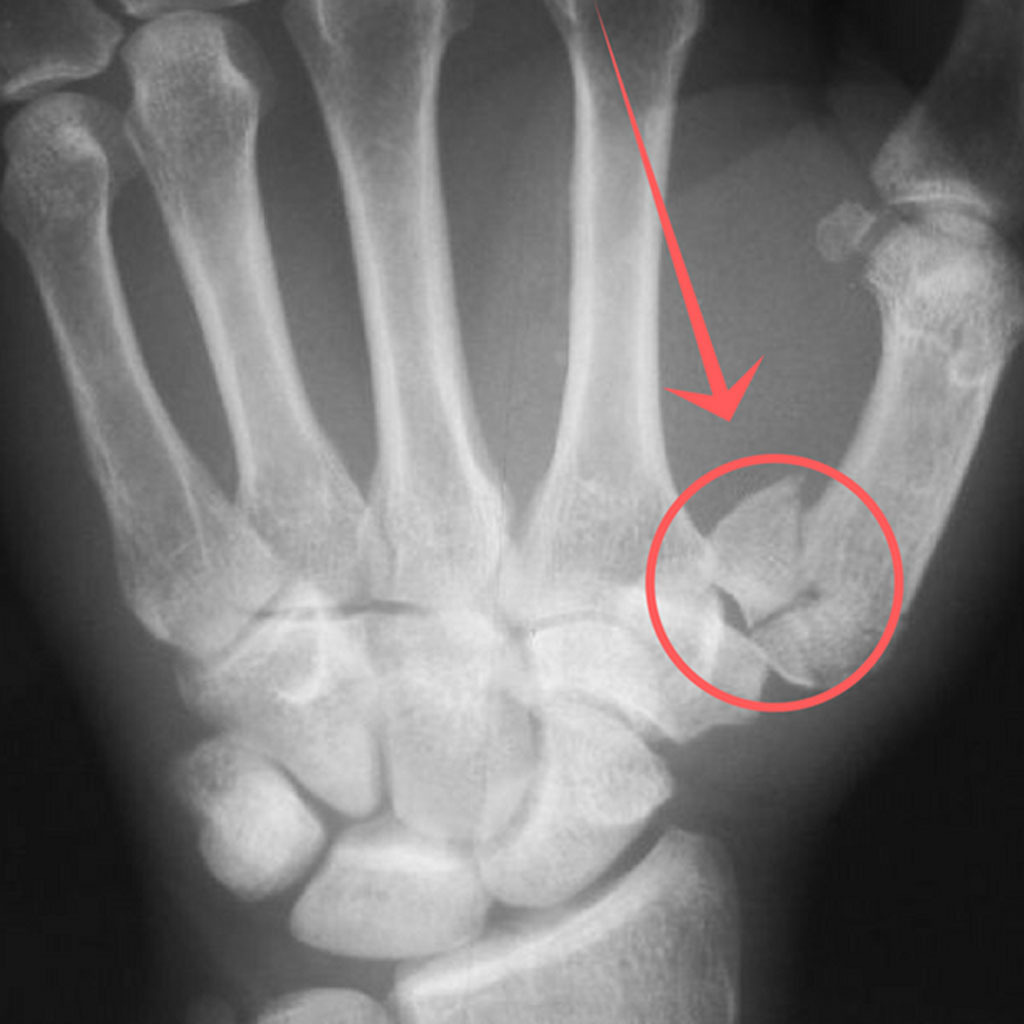

골절 유형

- 단순 골절: 뼈가 한 번 금이 가거나 깨진 정도로, 비교적 뼈 조각이 많이 어긋나지 않은 경우입니다.

- 복합 골절: 뼈가 여러 조각으로 나뉘거나, 뼈가 제 위치에서 크게 어긋난 경우입니다.

- 압박 골절: 압력에 의해 납작하게 뭉개지듯 부러진 형태이며, 골절 부위가 복합적으로 손상되기 쉽습니다.

발가락 골절 수술 치료

- 적용 시기: 복합 골절, 압박 골절, 뼈 조각이 여러 개로 나뉜 경우처럼 깁스나 스플린트만으로 회복이 어려운 경우.

- 치료 방식: 핀을 박거나 금속판을 대는 방법을 사용합니다. 골절 부위를 정확히 정렬하고 뼈가 잘못 붙지 않도록 하는 것이 핵심입니다.